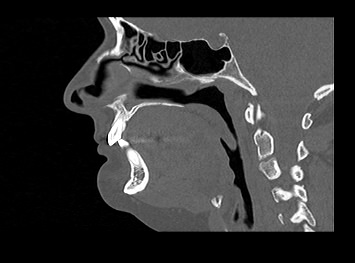

В куполе носоглотки находятся глоточные миндалины (при разрастании их называют аденоидами). В боковых отделах расположены устья слуховых труб (Евстахиевы трубы), спереди – хоаны (отверстия, соединяющие полость носа с носоглоткой).

В связи со своим расположением в непосредственной близости к полости носа и ушам, носоглотка часто подвержена развитию хронических воспалительных заболеваний, а также доброкачественных и злокачественных новообразований.

Одним из методов диагностики заболеваний носоглоточной области является мультиспиральная компьютерная томография. КТ носоглотки назначают при подозрении на рост новообразований, в случае хронического воспаления, при врожденных аномалиях строения носа и прилегающих к нему придаточных пазух.

Методика предусматривает использование рентгеновского излучения. Благодаря различной способности тканей поглощать рентгеновские лучи и последующей цифровой обработке полученных данных, удается получить изображения исследуемой зоны в мельчайших подробностях.

Инновационные цифровые приложения томографов позволяют получить снимки высокого качества и детализации, а также создать трехмерные реконструкции анатомической зоны исследования, что дает возможность рассмотреть пространственное расположение органов и патологических образований.